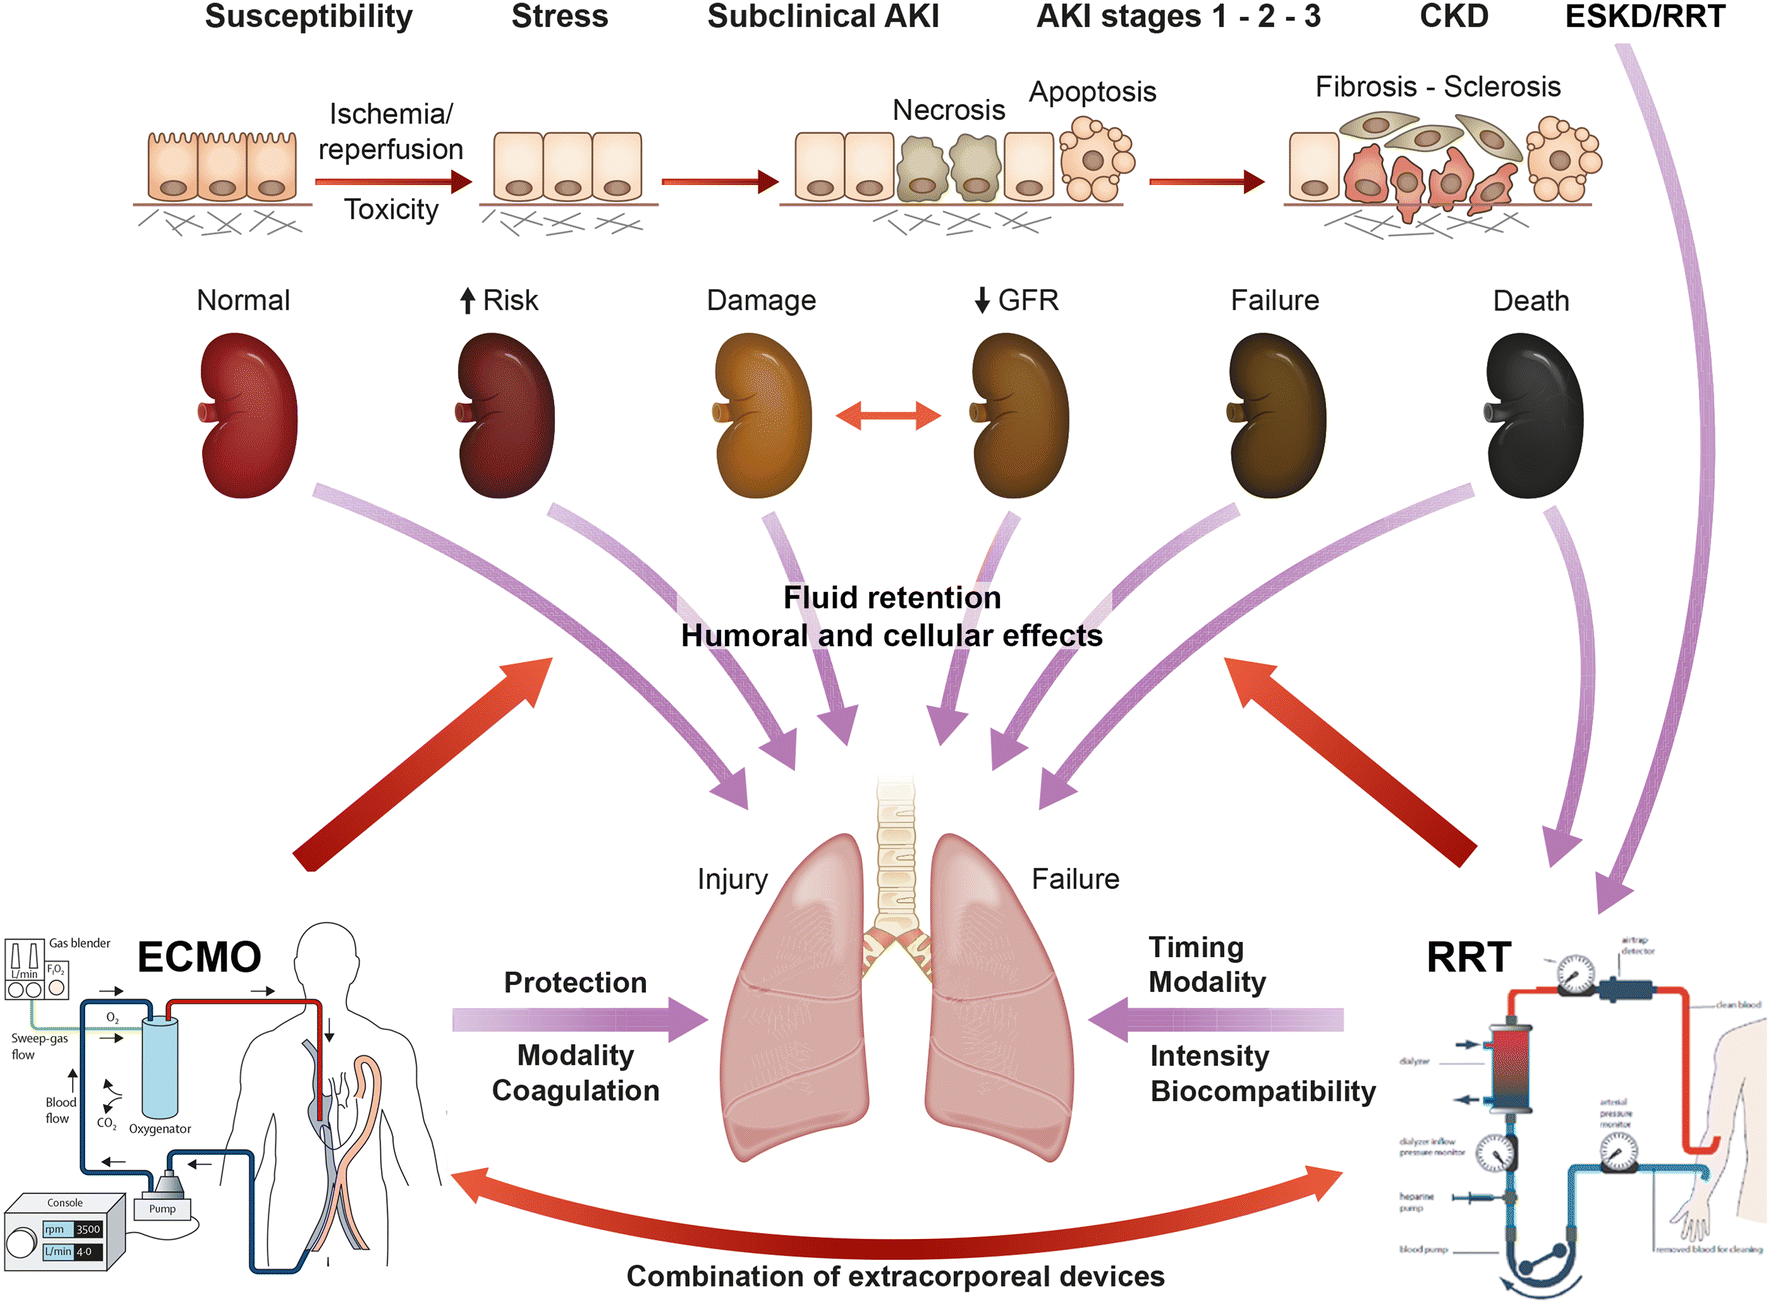

Umgekehrt kann es jedoch auch im Rahmen einer akuten Nierenschädigung zu einer zunehmenden Schädigung und Funktionseinschränkung der Lunge kommen. „Dies kann zum Beispiel durch einen Flüssigkeitsüberschuss bedingt sein, wenn die Niere aufgrund ihrer Schädigung eine adäquate Flüssigkeitsausscheidung nicht mehr aufrechterhalten kann. In weiterer Folge kann dies ein Lungenödem zur Folge haben“, erklärt Intensivmediziner Joannidis. Durch entsprechende vorsichtige Flüssigkeitsbilanzierung beziehungsweise Unterstützung der Flüssigkeitsausscheidung mit harntreibenden Medikamenten oder Nierenersatztherapie (Dialyse) könne dieser Komplikation, so ein Ergebnis der Untersuchung, vorgebeugt werden. Des Weiteren konnten verschiedene Effekte von extrakorporalen Systemen, wie eine „künstliche Niere oder Lunge“, auf die Organfunktionen aufgezeigt werden. „Insbesondere die Kombination von extrakorporalen Systemen stellt Ärztinnen und Ärzte vor neue Herausforderungen und Fragestellungen, wodurch auf diesem Gebiet sich einige neue Forschungsfragen ergeben haben“, sagt Michael Joannidis. So konnten insgesamt mit Ergebnissen der Untersuchung sowohl Empfehlungen für die direkte Patient:innenenversorgung als auch weitere Fragestellungen für zukünftige Forschungsschwerpunkte formuliert werden.

Die Niere als Warnsignalgeber